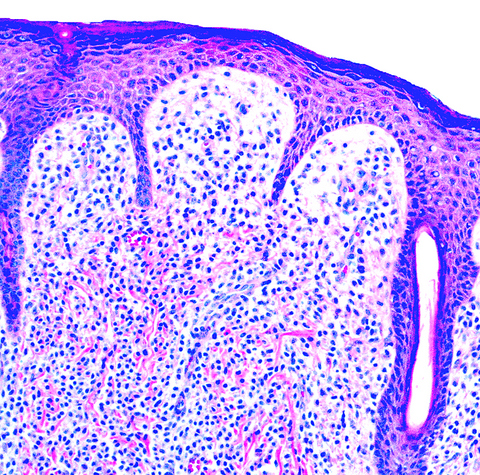

Microscopic (histologic) description

- Within the macules and plaque, mast cells are predominantly in papillary dermis

- Also edema of papillary dermis, subepidermal vesiculation

- In telangiectasia macularis eruptive perstans, features may be subtle, with increased mast cells around dilated superficial capillaries, basal cell hyperpigmentation of overlying epidermis, superficial lymphohistiocytic infiltrate

Microscopic (histologic) images

Differential diagnosis

- Normal skin or dermatoses:

- Must search to find mast cells even with special stains